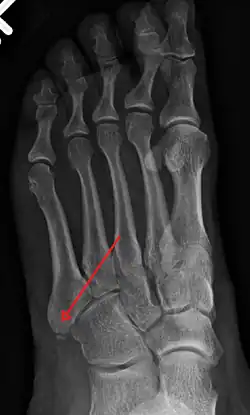

X-ray of foot. -